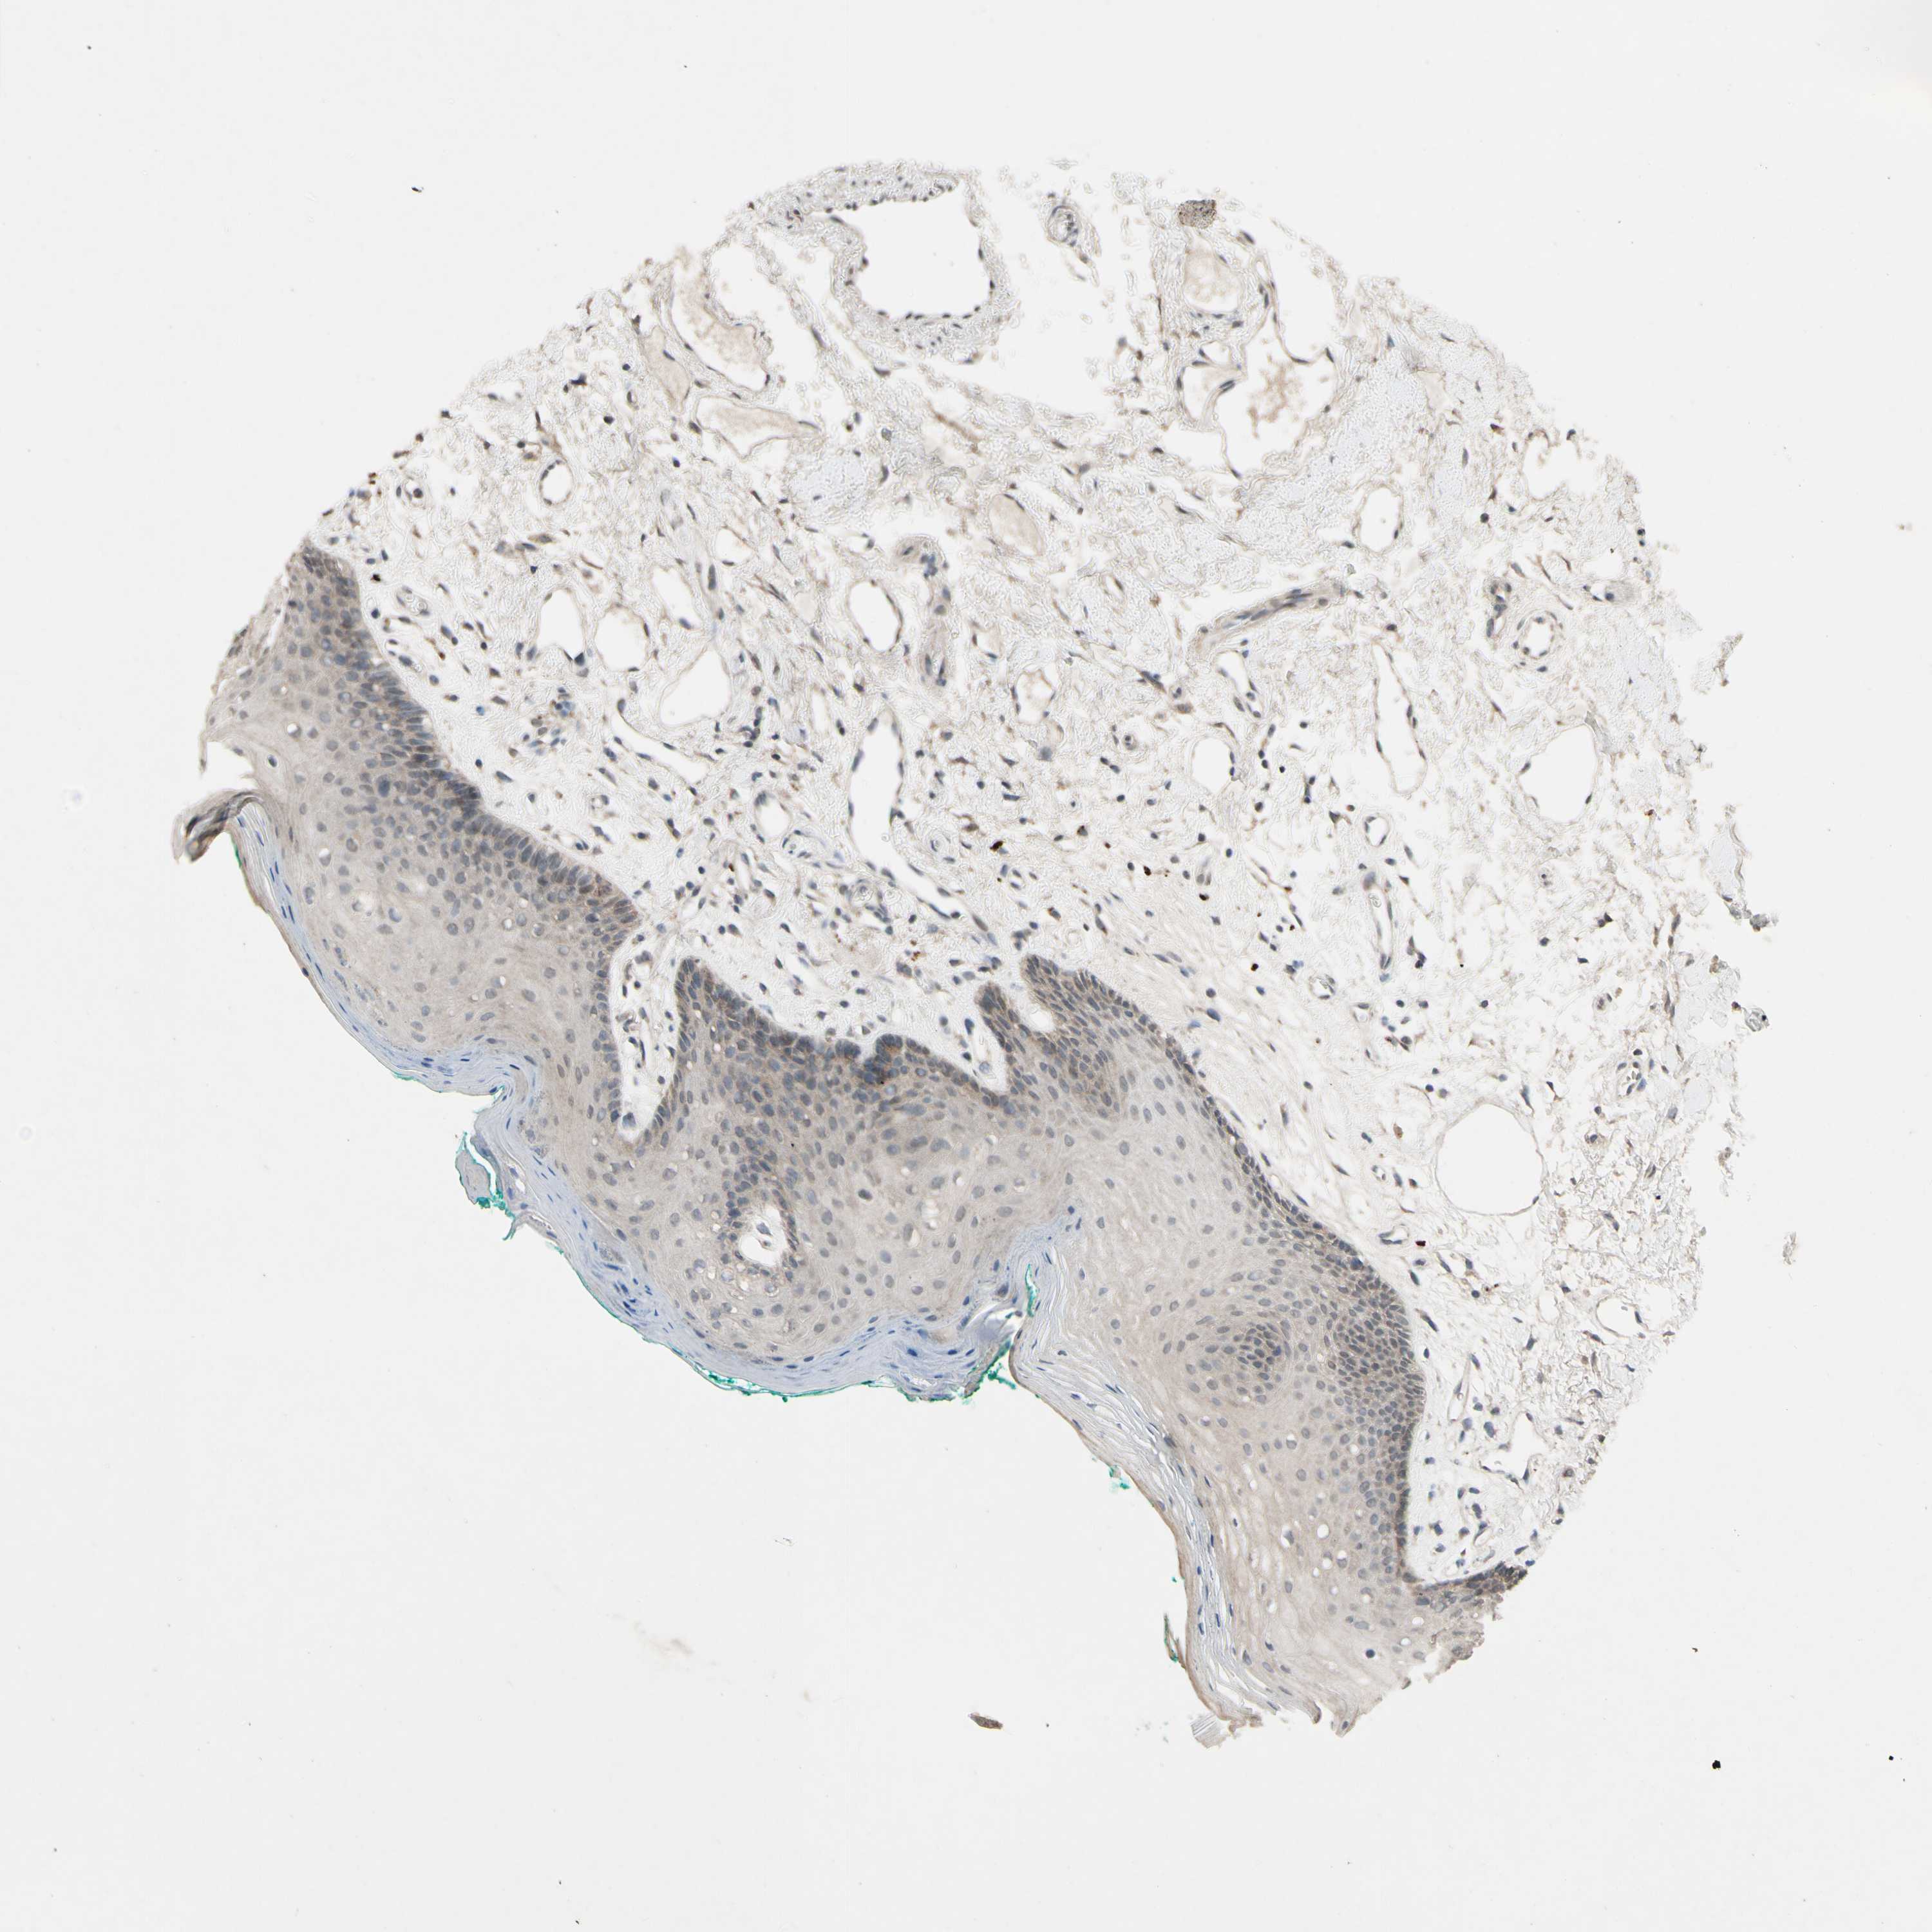

CDCP1